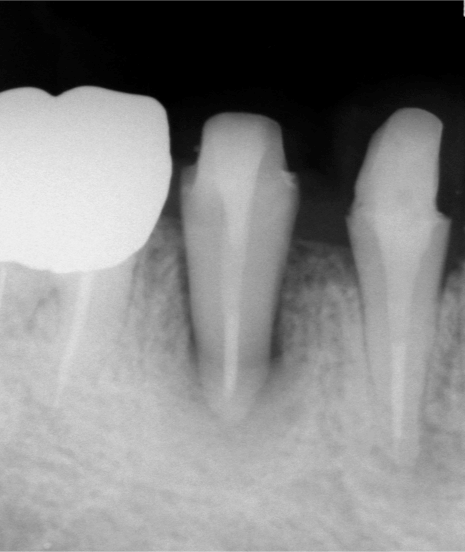

初診時のレントゲン写真です。虫歯が大きく、歯茎も腫れていました。診査の結果、根の治療が必要と判断し、行いました。

術後2ヶ月のレントゲン写真です。根の先の炎症が治りません。